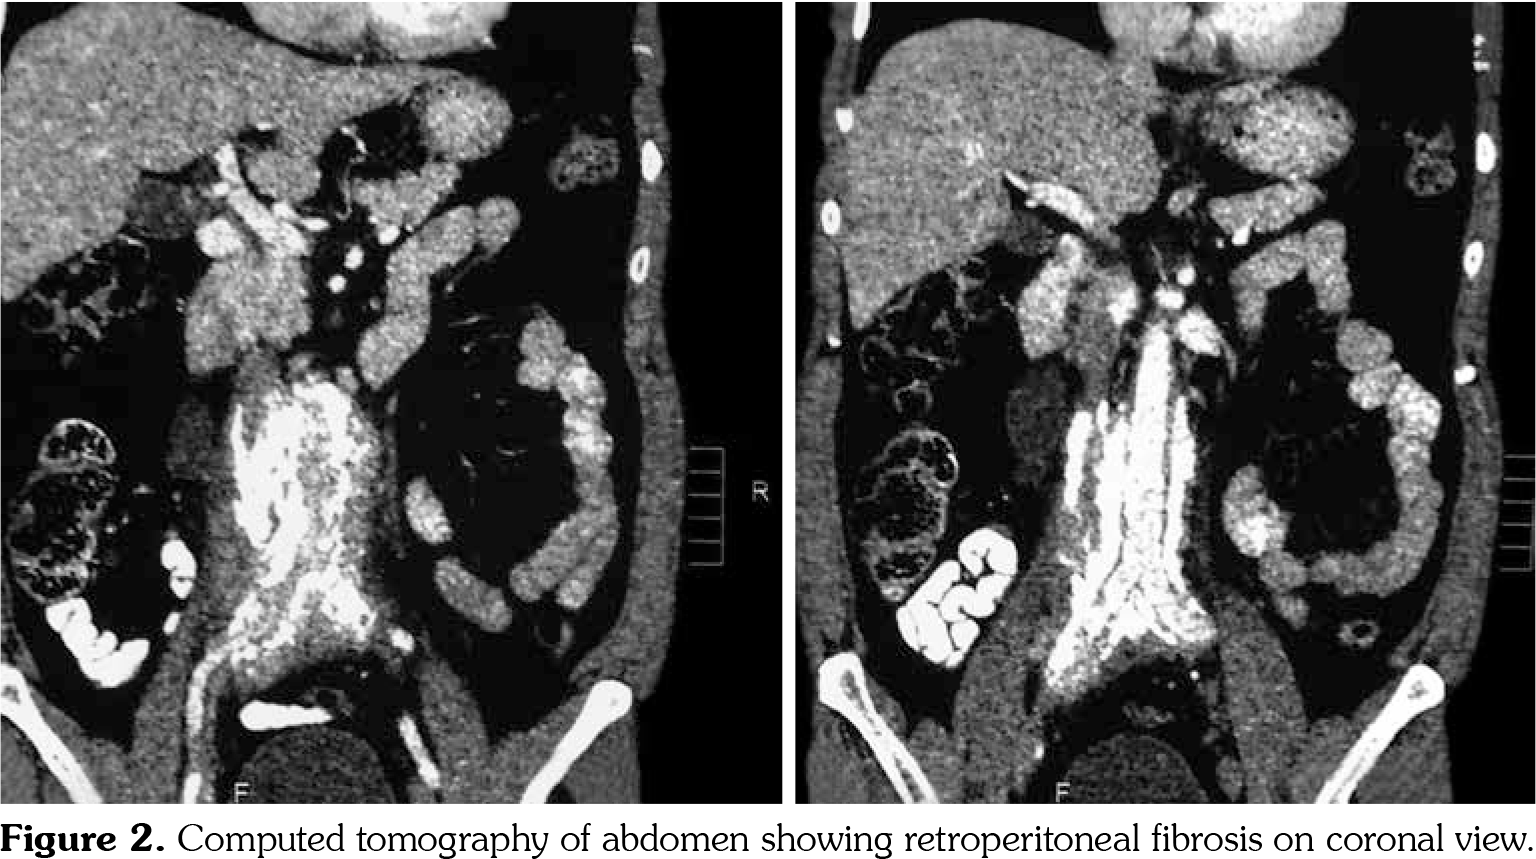

On investigations, his complete blood count was normal. Erythrocyte sedimentation rate was 88 mm in first hour. Random blood sugar was 93 mg/dL. His serum urea was 26 mg/dL and serum creatinine was 1.1 mg/dL. Liver function tests were within normal limits. Chest X-ray revealed non-homogenous opacities in bilateral lung fields. Pulmonary function tests revealed forced expiratory volume in one second (FEV1) of 61% and forced vital capacity (FVC) of 73%. FEV1/FVC ratio was 84%. Two-dimensional echocardiography was within normal limits. Ultrasonography of the abdomen revealed small-sized right kidney (6.9x2.9 cm) with dilated pelvi-calyceal system and dilated proximal ureter. Computed tomography (CT) of the abdomen revealed medial deviation of right ureter and presence of retroperitoneal soft tissue along infra-renal aorta and peri-caval area with calcification extending up to iliac vessels suggestive of RPF (Figures 1, 2, 3, and 4). High-resolution CT of the chest confirmed presence of interstitial lung disease (ILD). ANA profile (ENA) revealed that anti-U1 snRNP was strongly positive. Rest of the autoantibodies were negative. His serum immunoglobulin G levels were within normal limits. Thus, we arrived at a diagnosis of MCTD with RPF and ILD. He was started on mycophenolate 720 mg twice daily, hydroxychloroquine 200 mg once daily and deflazacort 6 mg once daily for MCTD, pirfenidone 400 mg twice daily for ILD and tamoxifen 20 mg once daily for RPF. On follow-up at six months, he was doing physically well. His symptoms of cough were reduced and dyspnea improved from NYHA class IV to class II. Repeat pulmonary function tests revealed FEV1 of 59%, FVC of 71% and FEV1/FVC ratio of 84%. However, repeat ultrasonography of the abdomen did not reveal any significant change in pelvi- calyceal system.

In 1972, Sharp et al.,[1] recorded a group of patients who had clinical features of SLE, SSc and PM with high titers of anti-extractable nuclear antigen antibody. They published it as a new disease entity: MCTD. Since then, there has been an increasing number of classification criteria published for the diagnosis of MCTD, namely, Kasukawa et al.[3] Alarcon-Segovia and Villareal[4] and Kahn and Appelboom.[5] There has been no consensus on clinical features owing to varied manifestations and frequent overlap of symptoms with other autoimmune conditions. However, high titers of antibodies against U1 snRNP have been found in most patients.[6] Our patient had symptoms of dysphagia, epistaxis and ocular sicca coupled with high titers of anti-U1 snRNP which led us to the diagnosis of MCTD. He also had pulmonary involvement in the form of ILD. One study showed 47% of cases of MCTD to have ILD.[7] The most frequent histological picture seen is non-specific interstitial pneumonia, followed by usual interstitial pneumonia and lymphocytic interstitial pneumonia.[8] RPF was first reported by Ormond[9] in 1948. It is a rare condition characterized by inflammation and fibrosis of the retroperitoneum, around the infra-renal portion of abdominal aorta and iliac arteries and usually entraps ureters and inferior vena cava.[10] A recent study reported incidence of RPF around 1.3 per 100,000 population per year in Netherlands.[11] The mean age of presentation is around 50 years with male predominance (2:1-3:1). Abdominal CT and magnetic resonance imaging are the investigations of choice for the diagnosis of RPF and they reveal a homogenous mass near the lower abdominal aorta and iliac arteries that surround and displace the ureters medially. Medical therapies for RPF include steroids, tamoxifen, other immunosuppresives such as azathioprine, mycophenolate and anti-CD20 antibody such as rituximab. In one single-center prospective observational study of 55 patients with RPF treated with tamoxifen monotherapy for a minimum of two years, 47 (85%) patients reported substantial resolution of symptoms after a median treatment duration of three weeks. There was a mass regression in 39 (71%) patients at four months and 47 (85%) patients at eight months of follow-up, respectively. Recurrence- free survival in patients with treatment success after post-treatment follow-up of 21 months was 68%.[12] To our knowledge, there is no previously published case report on presence of RPF in a patient of MCTD. This is indeed a rare occurrence.